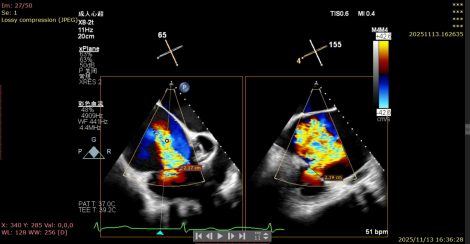

1.TR Reduction: Overall reduction greater than 3+ (decreased from massive 6+ to moderate-to-severe 3+).

Massive 6+

Moderate-to-Severe 3+